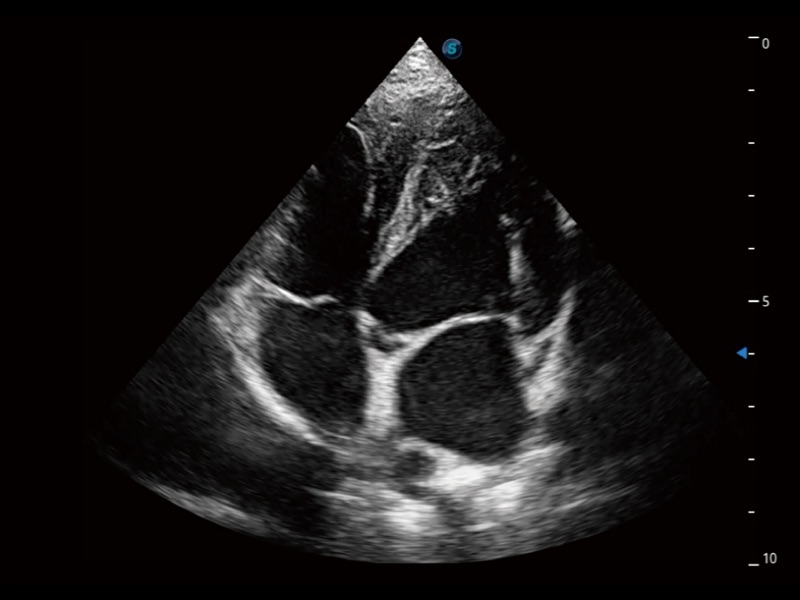

ProPet 70 进一步提升了微米成像算法,更加注重对基础原始图像的还原和保留,在有效减少斑点噪声、增强组织边界显示的同时,避免过度优化丟失真实的解剖信息。

通过360度任意调节3条M型取样线,在同一心动周期上观察心脏不同位置的运动曲线,得到准确的心功能测量数据,有效评估心肌运动及左心室功能。

ProPet 70专为动物医生设计,对不同的动物体型和生理结构作出了针对性的优化。通过动物影像专用软件,可满足个性化的应用需求,帮助动物医生获得更精确的诊断数据。